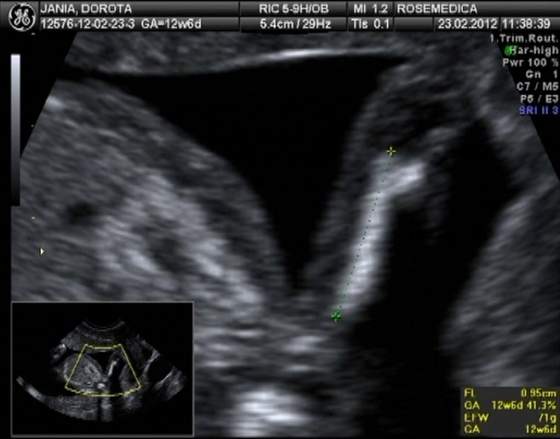

usg robil i dopochwowe i brzuszne bardzo dlugo i bardzo dokladnie i bardzo delikatnie - cieszylam sie, ze dlugo, bo sobie caly czas na ludzika patrzylam. Przez to dopochwowe widac go duuuuzo wyrazniej ale o tym zaraz. poza tym zrobil cyto i normalne badanie ginekologiczne i dziwil sie, ze na poczatku ciazy nie mialam ale teraz sobie przypominam, ze chyba w listopadzie mialam, wiec pewnie ginka uznala, ze bez sensu ponawiac.

ludzik byl niesamowity! wierzgal, wycigal sie, nozki wypychal, lapki wyciagal jakby chcial boksowac, pupa sie wykrecal, potem spowrotem buzia do usg. wiercil sie niesamowicie. z 10 min musielismy czekac, zeby sie dal zmierzyc gagatek. powiem nieskromnie, ze ten bubusiowy dzidz w porownaniu do mojego gowniarza kochanego to len straszny ;-)

powod mojego zlego samopoczucia ma juz cale 39 mm